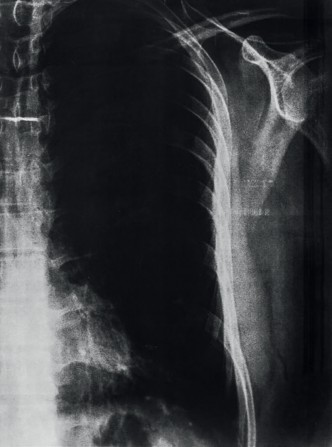

El vacío existencial es un término que, bajo la lógica precedente, se considera dentro de la dimensión de lo real. El objetivo de esta propuesta es identificar el vacío existencial en el cuerpo a través de un escaneo por rayos X del tórax (imagen 4). El vacío se define como un sin sentido de la vida, una insatisfacción persistente y una realidad insoportable.

La imagen cuatro fue generada mediante una técnica de diagnóstico médico de rayos x. Se sometió a un proceso de escaneo en alta resolución y se editó para acentuar sus elementos mediante una corrección de color en un editor de imagen digital. Se usó este método porque la radiografía en película necesita de una fuente de luz para identificar sus elementos; al escanearla, es más fácil visualizar los detalles.

Se aplicaron diez filtros de color, aumentando el brillo y el contraste. Las imágenes 4, 5 y 6 fueron las que reconocieron más elementos. La imagen en azul muestra la matriz impregnada por los rayos gamma que atraviesan los tejidos de los pulmones y el corazón, registrando el vacío: lo único que se percibe son las vértebras dorsales, las costillas y parte de lo que (se supone) son las escápulas. En la imagen 5 se observa un enmarañado tejido en la parte central baja que acompaña a las vértebras cerca del estómago. Esta región se acerca demasiado a la estética computacional de arte generativo y se reafirma la trascodicficación de patrones provenientes de la naturaleza, en este caso del cuerpo humano.

Por último, la imagen número 6 muestra el vacío existente en el tórax y explica lo real a partir de una construcción ideal imposible, ya que la caja toráxica no muestra órganos ni tejidos, registra algunas texturas de color blanco pegadas a las vertebras. En la mayor parte del centro del pecho se registró el color negro como ausencia.

Las imágenes resultantes tienen como finalidad ser un proceso alterno de creación de imágenes en CG-art que no representan, presentan el fenómeno de estudio. Existe el dolor como síntoma en la dimensión de lo real. Estas imágenes podrían mostrarnos un atisbo del vacío existencial ocultado en la realidad, es evidente antenuestros ojos y oculto al mismo tiempo: ceguera episté- mica de la condición humana.